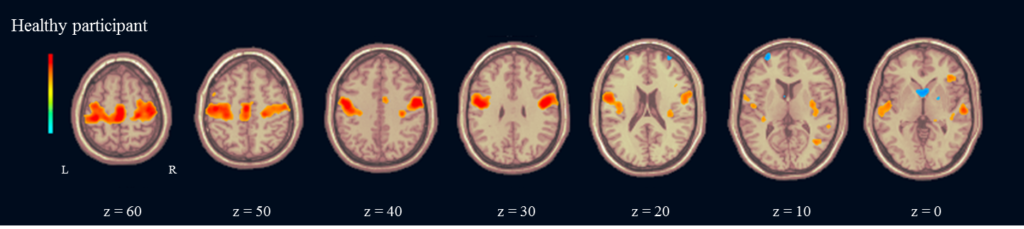

例えば,健常人の中心前回(運動野)は,同側の中心後回や対側の中心前回・中心後回,補足運動野などとの間に強いconnectivityが認められ,両側の脳が協調していることが分かります(Figure 1).